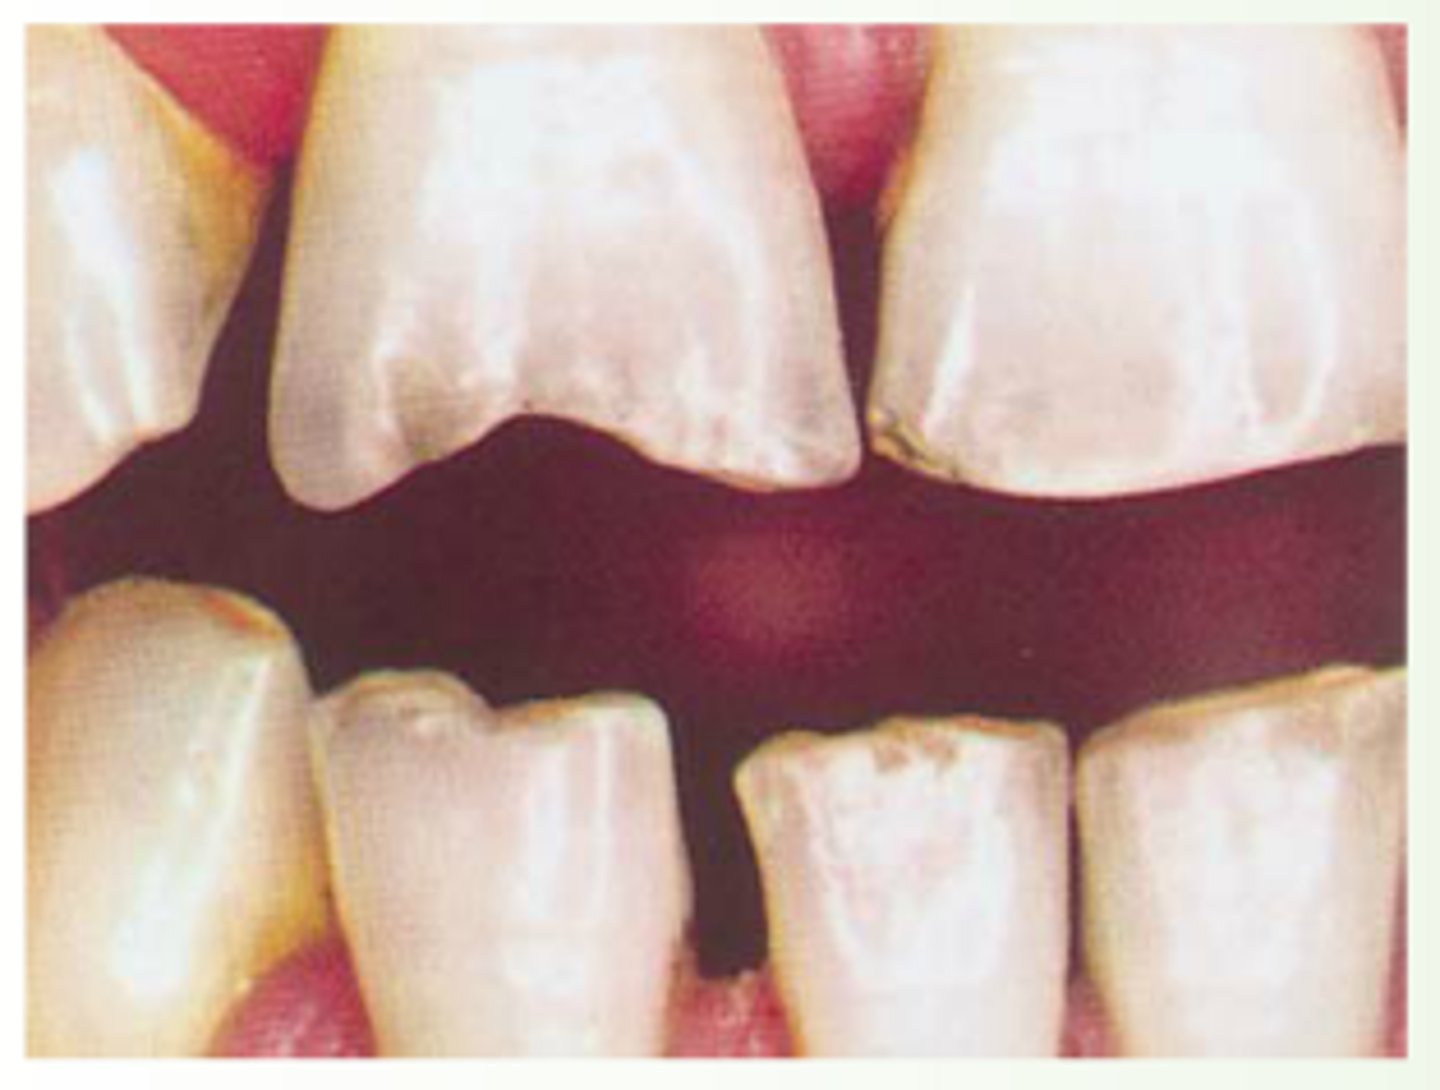

hutchinson's teeth

smaller teeth, widely spaced, notched surface

congenital syphilis

<p>smaller teeth, widely spaced, notched surface</p><p>congenital syphilis</p>